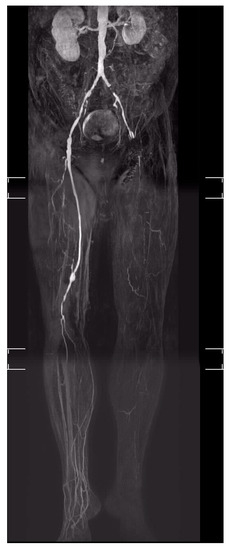

5.12. Arterialisation of the Deep Leg Veins (DVA or Deep Vein Arterialisation)